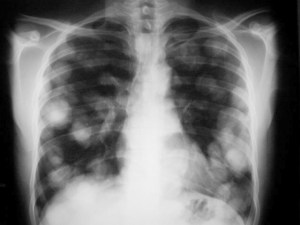

SIGNO DE LA SUELTA DE GLOBOS

La presencia de múltiples nódulos pulmonares bien definidos de distribución bilateral y aleatoria, de diferentes tamaños, es muy sugerente de metástasis pulmonares. El nombre del signo es muy gráfico.

El caso que mostramos corresponde a un paciente con metástasis de seminoma. Abajo, la imagen de TC del mismo paciente.